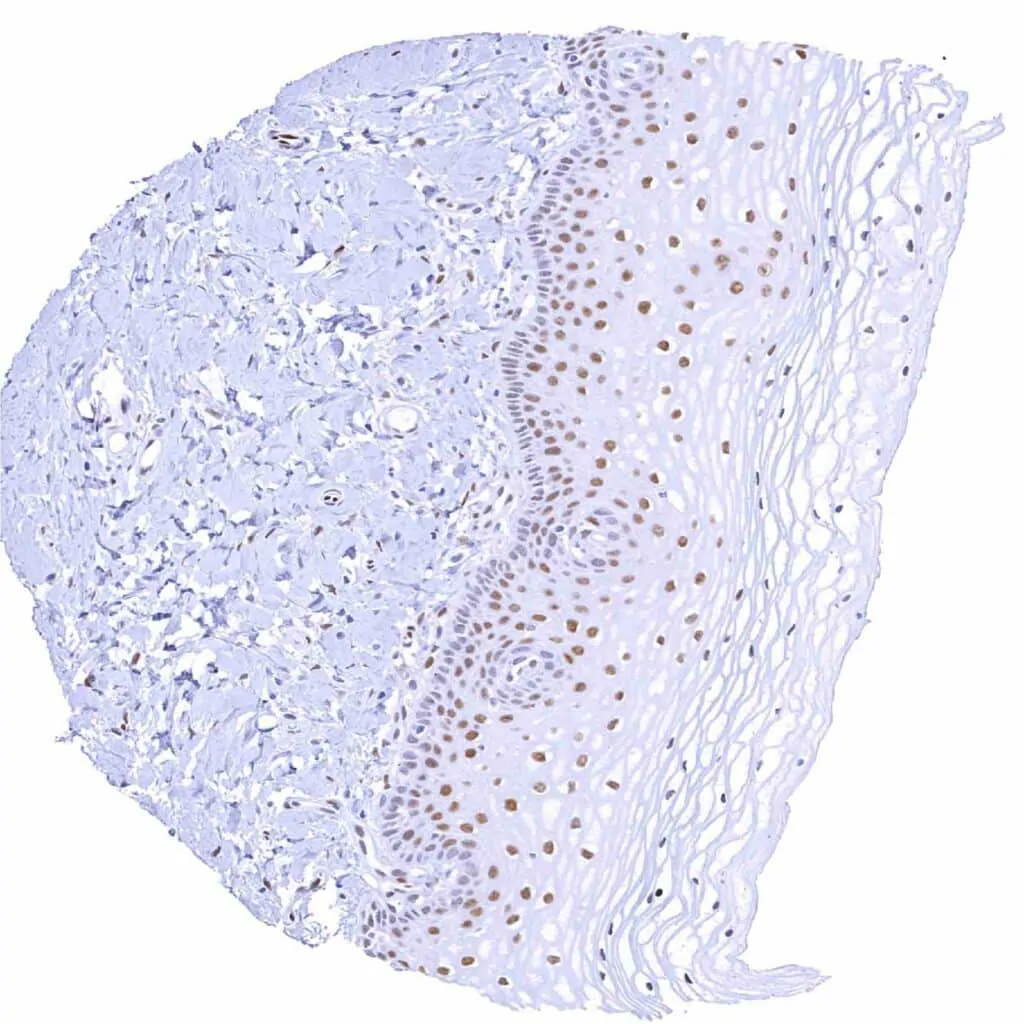

Uterus, ectocervix – Moderate TLE1 staining of squamous epithelial cells, predominantly of the suprabasal cell layers